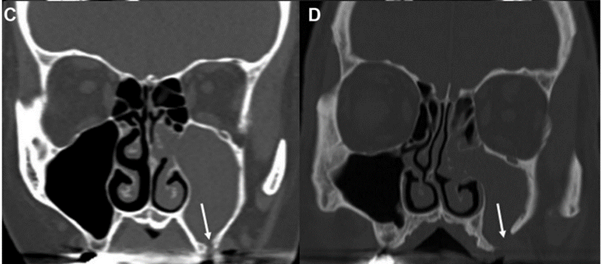

CT显示单侧上颌窦混浊

CT 上现实的可能的牙科病变

鼻内镜检查单侧中鼻道脓性物(下图)